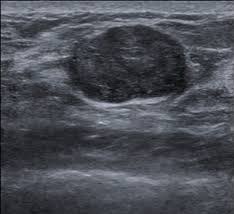

والذي يؤكد على وجود الورم ونوعه الحميد أو المشتبه به ويكون إما بالاشعه الصوتيه للنساء دون ٣٠عاما أو بالماموغرام والصوتيه لل ٣٠عاما وأكبر

8️⃣يميز الفحص الشعاعي بين التكتلات الصلبه والسائلة والتي تدعى بالاكياس وايضا صفاتها التي تشير الى كتلة حميده غير مقلقة أو الى كتلة فيها اشتباه تستدعي إجراء الخزعة

9️⃣ أنواع الأورام الحميدة عديدة اكثرها شيوعا

-أورام ليفية: تنشأ في الأنسجة الضامة حجمهابين 1-3 سم أوأكبر من ٥ سم وظهورها لا يجعل المرأة المصابة بها أكثر عرضة من غيرها للإصابة بسرطان الثدي.هي شائعة الحدوث بين كثير من النساء والفتيات خصوصا بين 15 - 35 و

🔟-كيس الثدي البسيط

مملوء بالسوائل يتطور عادة في الثلاثينيات والأربعينيات من العمر. قد تظهر فجأة و تسبب ألامًا شديده تضطر الطبيب الى سحب وتصريف السوائل لتخفيف الالم